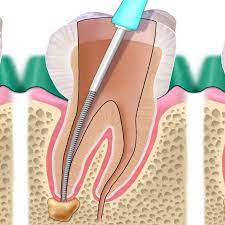

Il trattamento endodontico prevede la rimozione fino alle radici del dente della polpa danneggiata e nella sua sostituzione con un’otturazione permanente. In questo modo vengono elimitai tutti i batteri che si erano accumolati e che hanno causato il danno e il dente una volta riparato potrà tornare a svolgere la sua funzione.

Il trattamento prevede l’utilizzo dell’anestesia locale per neutralizzare il dolore e tenerlo sotto controllo, a seguito della terapia nelle ore successive è possibile sentire un indolezimento più o meno persistente che può essere controllato grazie all’assunzione di analgesici.